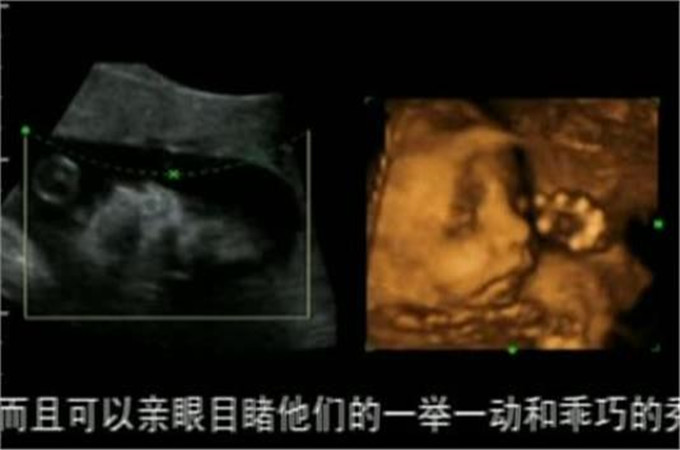

孕妇怀孕以后需要隔段时间做检查,每次检查都是必不可少的,只有定时的检查才能了解宝宝的情况,了解宝宝是不是健康。其中一个项目孕妇都不陌生,那就是四维彩超,孕妇在做这个检查的时候可以看到肚子里的宝宝,大概的模样还是能看的清楚的,那种感觉让孕妇感到很奇妙。

通过四维彩超这项产检,可以给医生一个很好的观察,看到宝宝的发育情况是不是完好,通过清晰的照片了解到宝宝的各个部位,其中可以排除宝宝的发育不良问题,从而可以及早的做出判断,这也是为了孕妇和宝宝都达到健康的标准。

有一些胎儿的先天性疾病会给家庭带来苦恼,及早的通过四维彩超检查可以有效的排出和避免很多问题出现,这也是最好的预防手段之一。所以根据医生的建议定期做检查,尤其是四维彩超是很关键的,绝对不要掉以轻心。